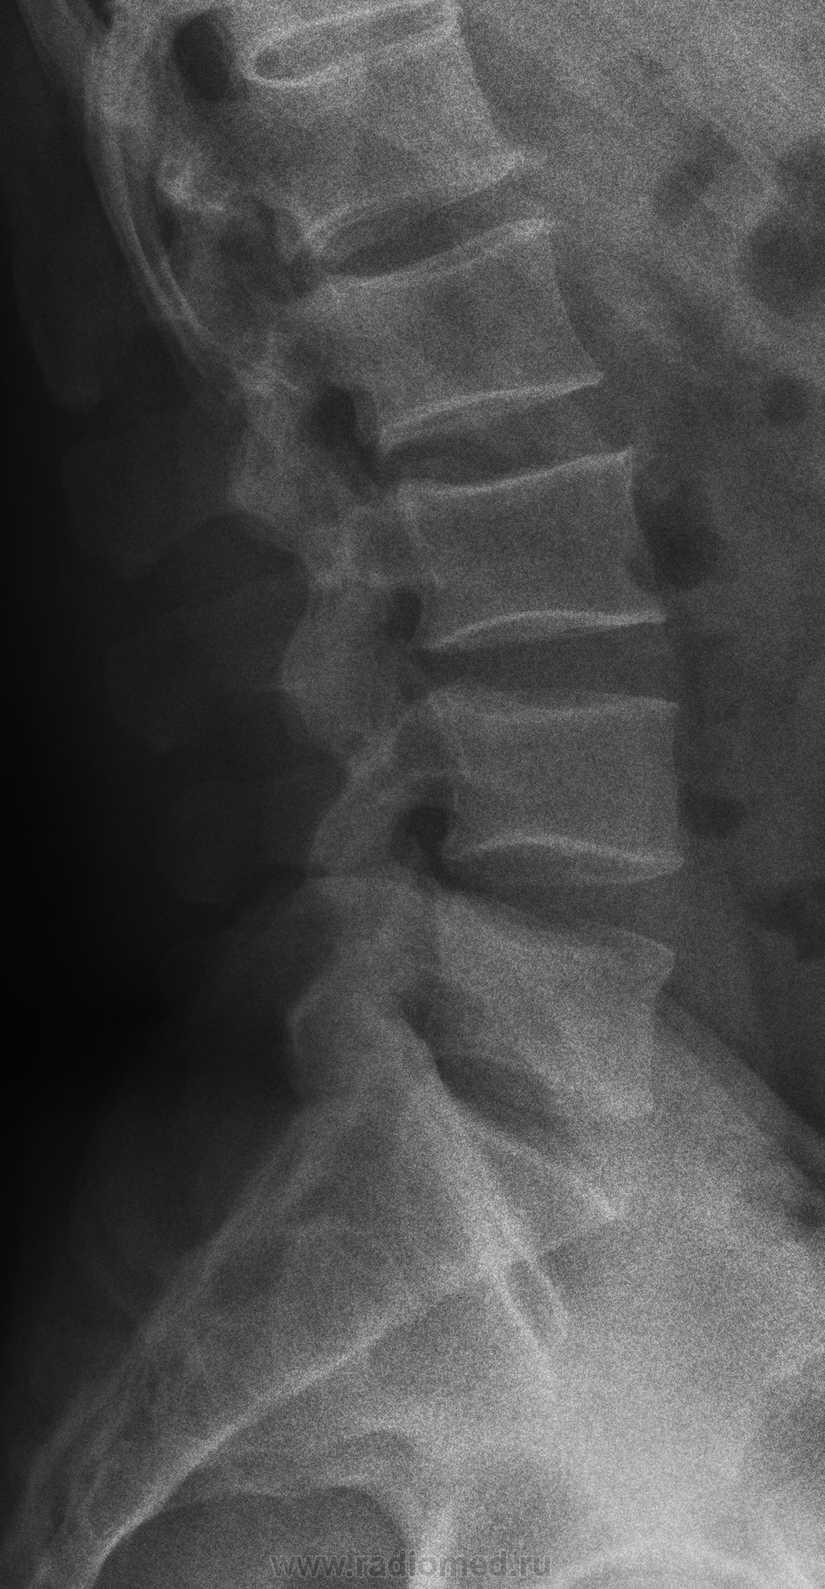

Рентген поясницы: анатомические особенности и медицинские исследования